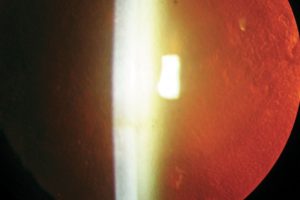

Un implant photovoltaïque sans fil sous-rétinien pour la DMLA atrophique évoluée par Pauline Eymard L’implant PRIMA est un implant de 2x2 mm et de 30 µm d’épaisseur, placé en position…